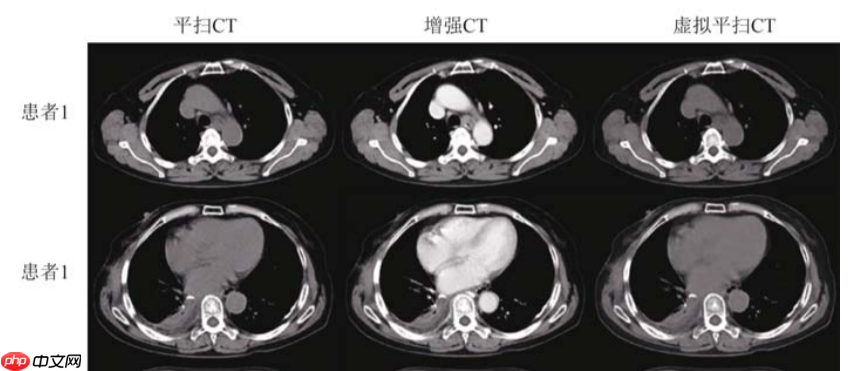

[1]高留刚, 李春迎, 陆正大,等. 基于卷积神经网络生成虚拟平扫CT图像[J]. 中国医学影像技术, 2022, 38(3):5.

【1】文章使用Unet对增强CT数据进行训练,最终预测生成对应的虚拟平扫CT图像,达到只需要对患者扫描一次CT即可,避免患者接受过多的放射辐射。